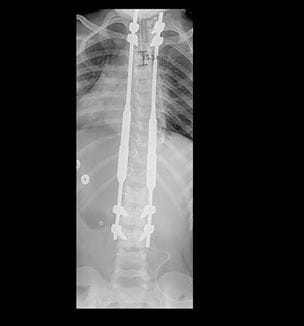

It's MAGEC: Helping Children with Scoliosis

Magnetically controlled growing rods help children with early onset scoliosis avoid multiple surgeries - Innovations in Orthopaedics - Winter 2019